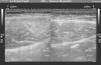

A pesar de los 7 días transcurridos, se observa una disrupción del correcto patrón fibrilar con sufusión hemática que invade la totalidad de la lesión y edema perilesional (figura 1, figura 2). El examen ecográfico también mostró una imagen fibrosa que, una vez interrogado el paciente, se concluyó que correspondía a una lesión antigua en el mismo vientre y asintomática en el momento de la consulta (figura 3).

Figura 3. Cicatriz fibrosa de una antigua lesión muscular en recto abdominal del mismo jugador.